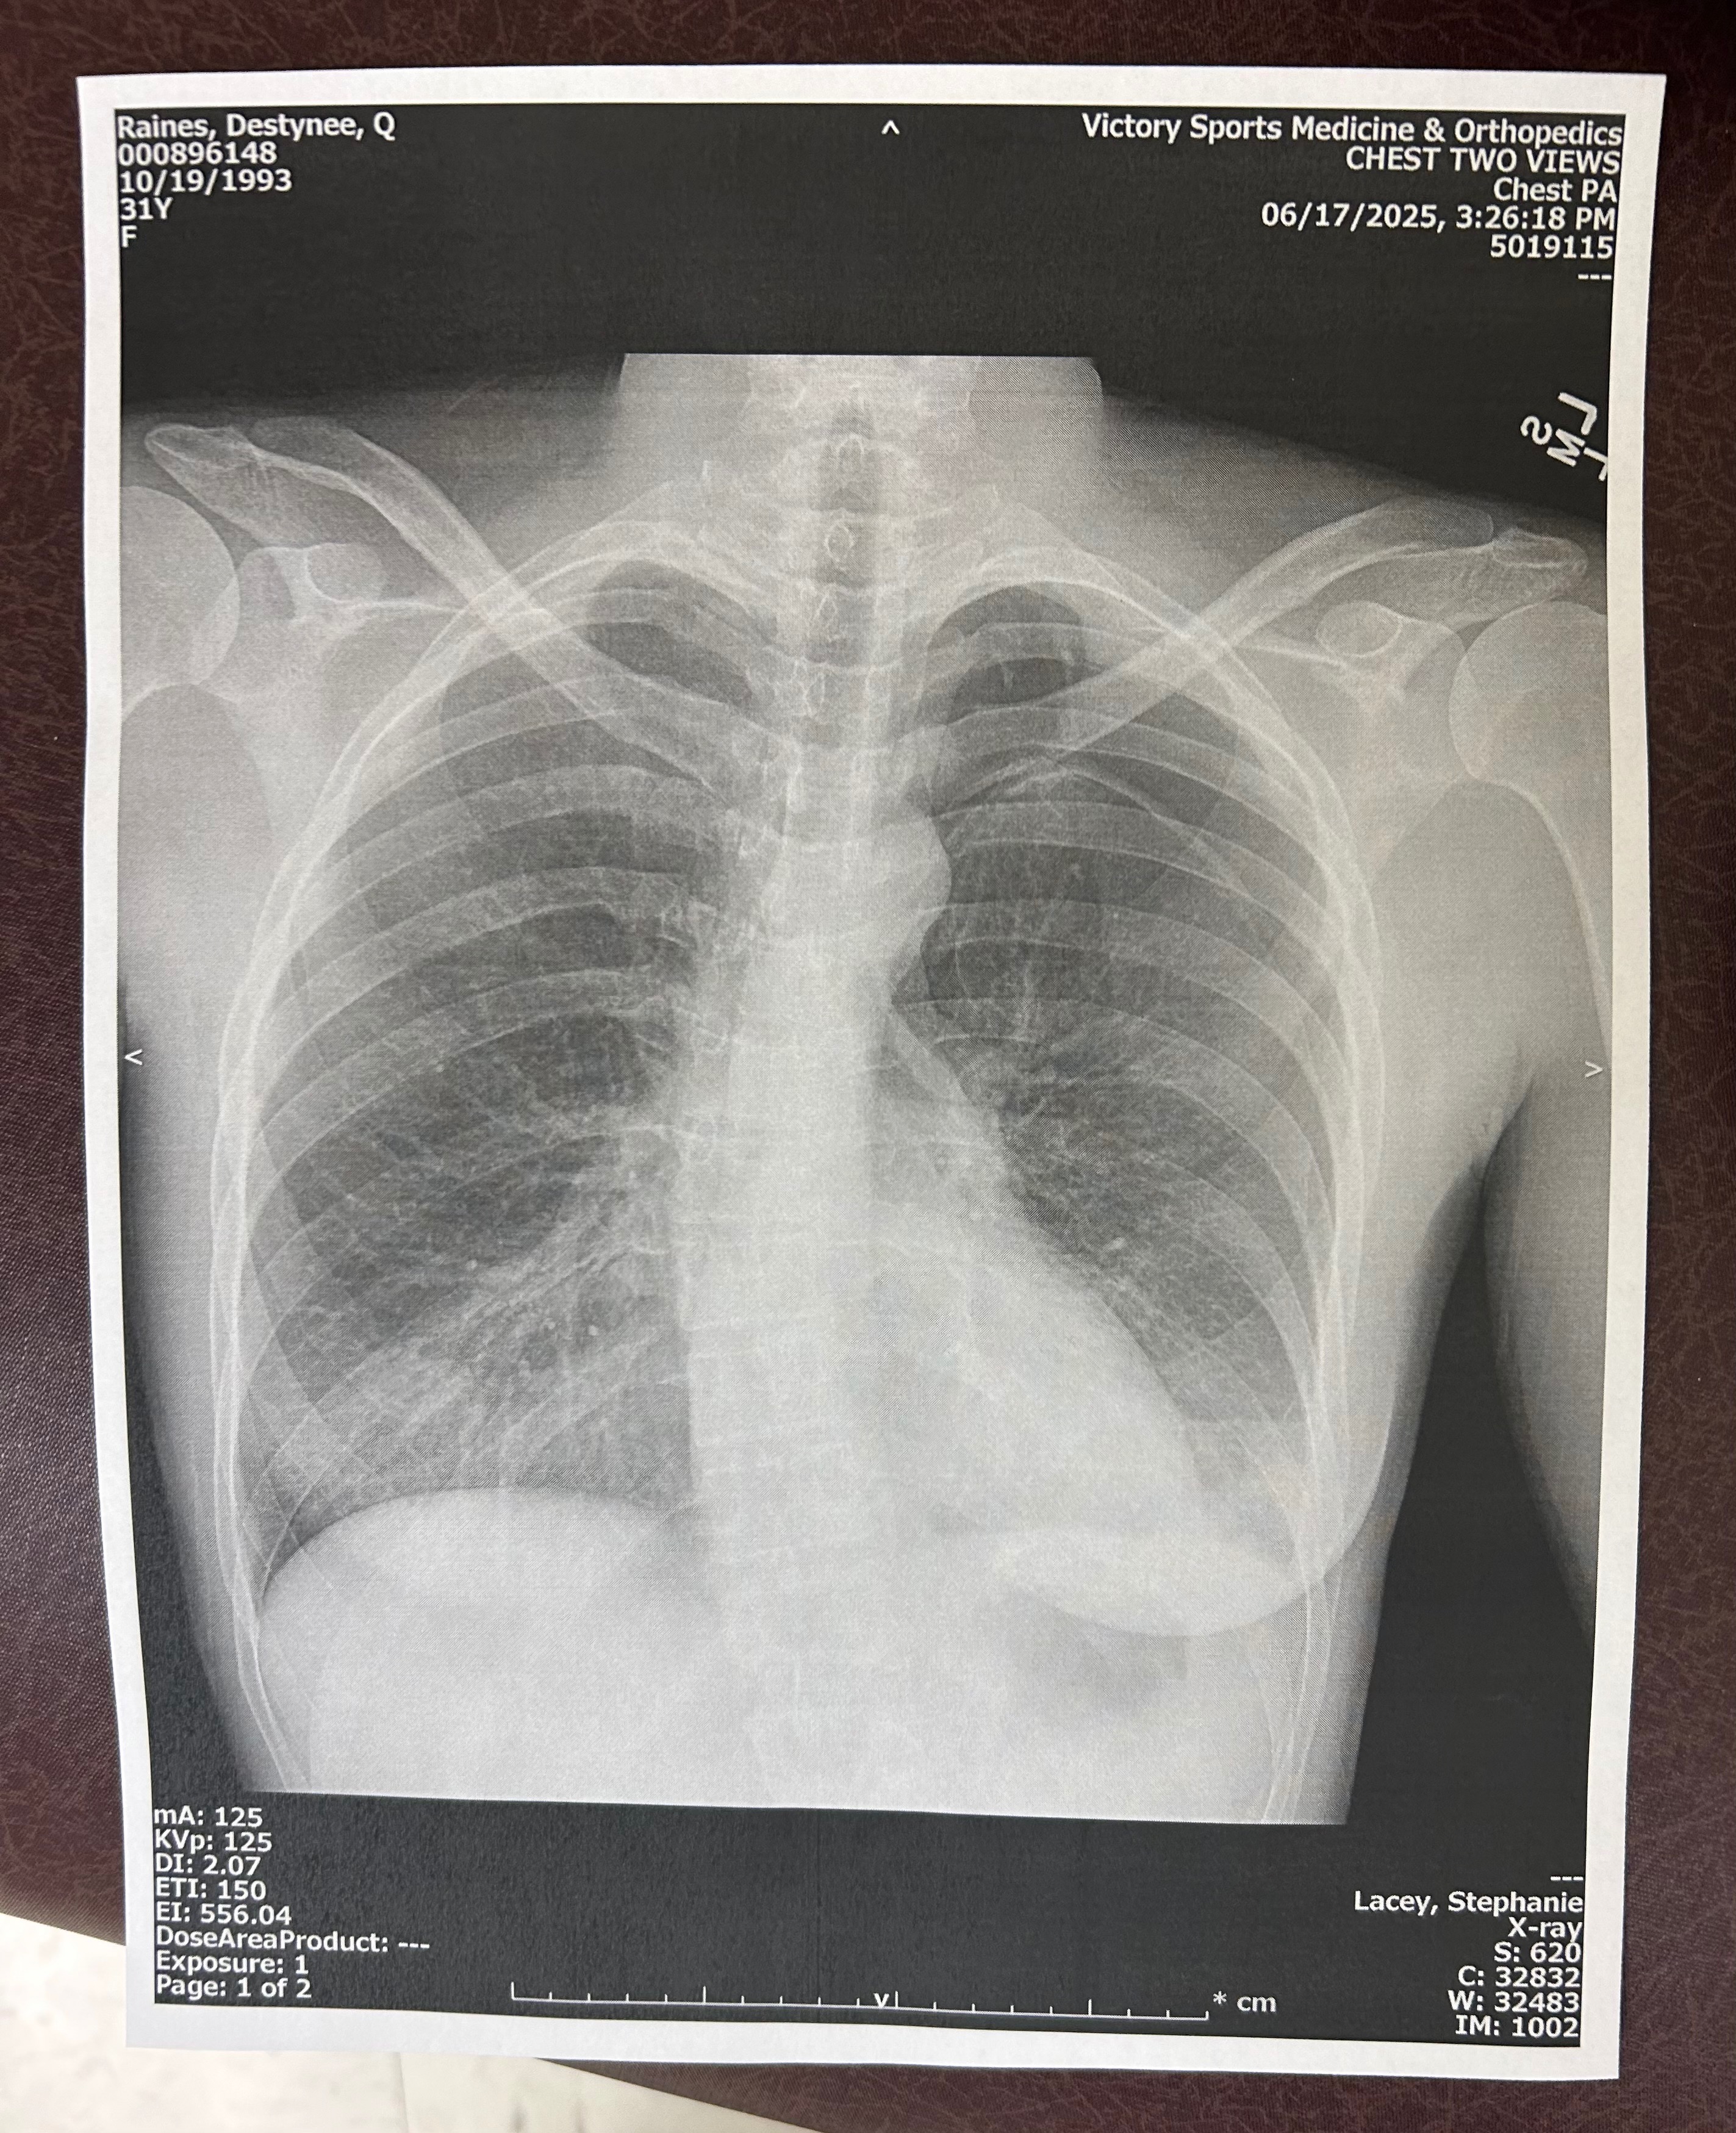

I was getting ready for work and had some serious chest pain. I thought I was possibly having a heart attack, but I knew that wasn’t quite it because it became extremely hard to breathe. I took some acetaminophen and propped my body up on the bed and waited for Jay to bring me to urgent care.

When we arrived, it was apparent that my lung had collapsed (pneuma) spontaneously. I refused to take an ambulance, and we drove to Auburn where I had an emergency procedure to reinflate the lung and drain the fluids. I had two tubes in my chest when I woke up from sedation, and I was in excruciating pain, which was not supposed to be the case with all the morphine I was on. Internal bleeding began, and I started leaking from the tubes, and it became imperative that I got to Strong Memorial Hospital as quickly as possible because it was now life or death.